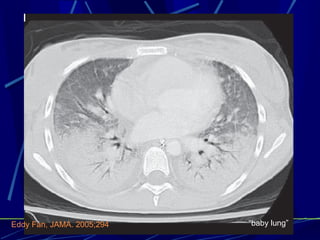

Eddy Fan, JAMA. 2005;294

“ baby lung” Eddy Fan, JAMA. 2005;294